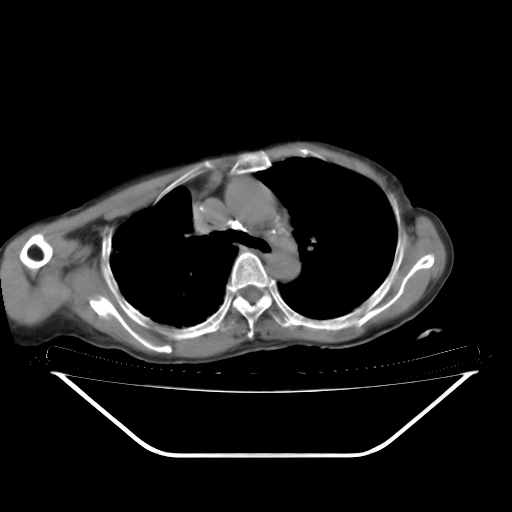

女70 反复咳喘心悸10余年,再发加再重伴双下肢浮肿8天入院。有肺结核病史20余年。

临床诊断:copd

双肺弥漫性间质性改变,内夹杂斑片状影,考虑肺水肿伴感染可能性大。右胸廓塌陷,右胸膜增厚粘连,心包积液

1)考虑间质性肺炎。2)右肺上叶结核并右肺上叶肺不张,右肺上叶支气管内膜结核不排除;两肺门及纵隔多发淋巴结钙化。3)心包积液;冠状动脉钙化。

1双肺间质性改变伴磨玻璃状影,考虑肺水肿伴感染可能性大。2心包积液。冠状动脉钙化。3右胸廓塌陷,右胸膜增厚粘连.

右肺支气管内膜明显增厚 变窄,并凹凸不平,右肺内见广泛的渗出 结节及斑片状混杂阴影。左肺下叶胸膜下渗出性致密影,双侧渗出影局限在双肺下部。另:左侧胸腔少量积液,心包肥厚伴积液。心脏增大。右侧陈旧胸膜病变伴胸廓塌陷,纵隔淋巴结钙化。多考虑:1 心源性肺水肿伴肺内感染 心包积液 肺淤血。2 右肺支气管内膜癌伴肺泡转移不除外。3 陈旧结核!